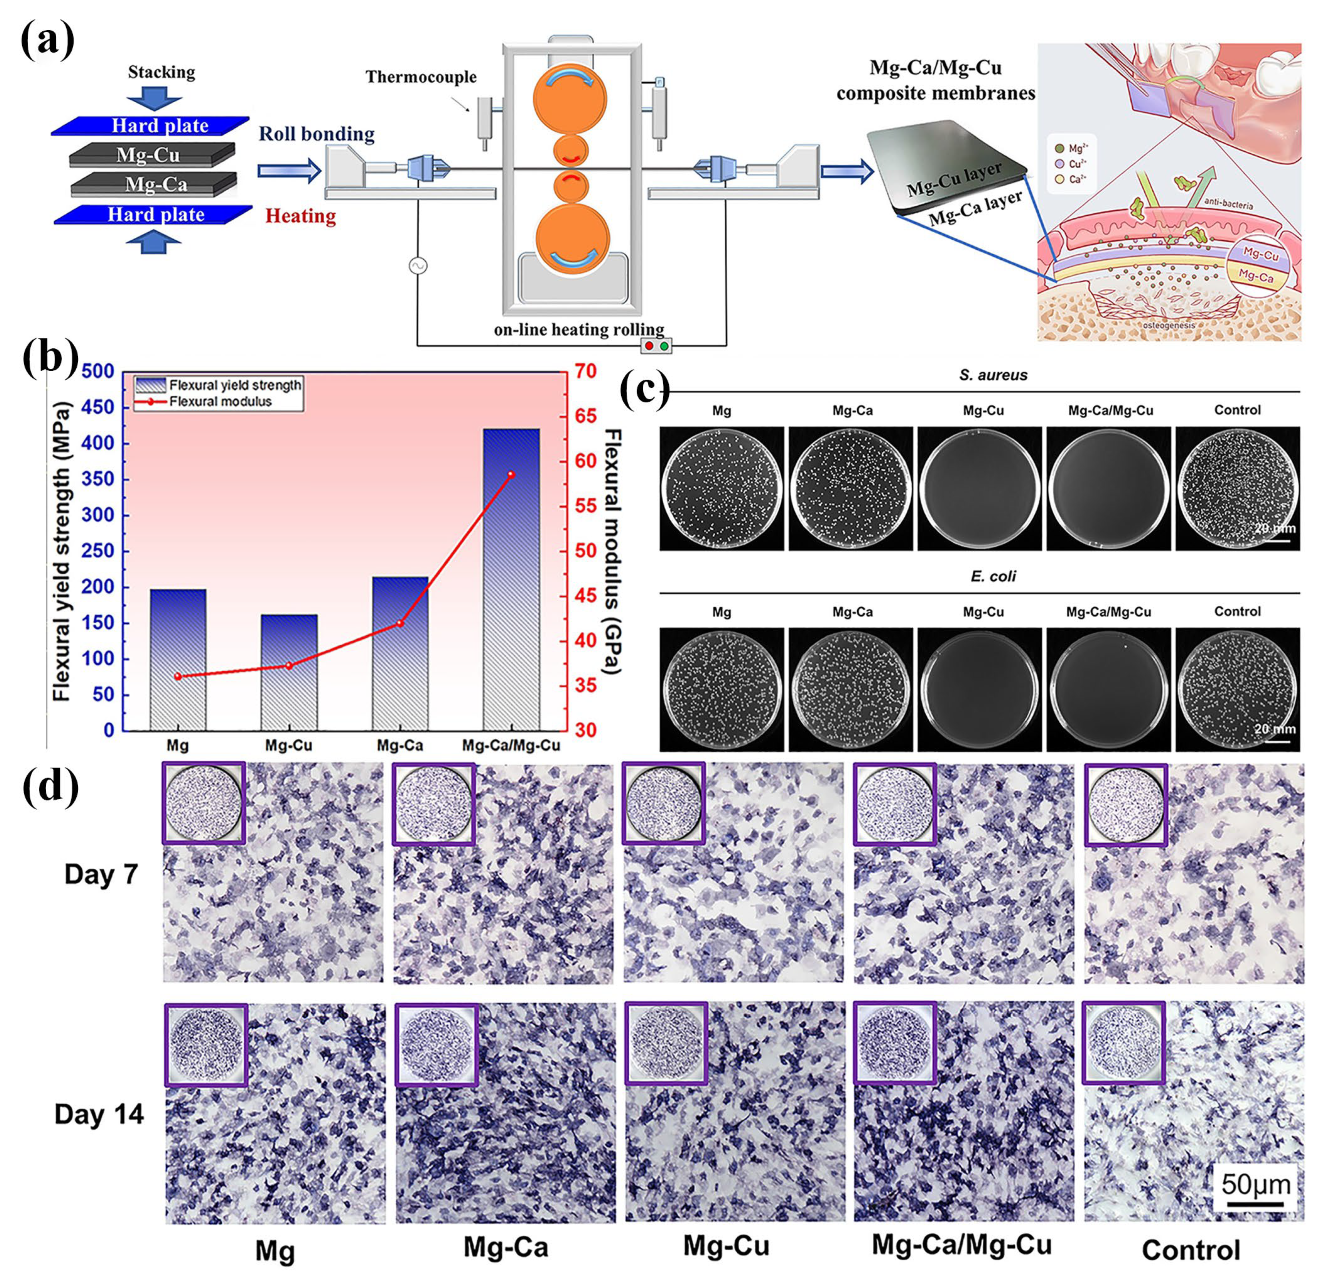

3.6. Oral Implant

- Shan, Y.; Qiao, B.; Ouyang, S.; Du, C.; Zhao, L.; Wang, G.; Ye, J.; Xiong, Y.; Wei, Y.; Song, J.; et al. Biodegradable Mg-Ca/Mg-Cu bilayer membranes with enhanced mechanical, osteogenesis and antibacterial performances for GBR applications. J. Magnes. Alloys 2024, 13, 792–809. [Google Scholar] [CrossRef]